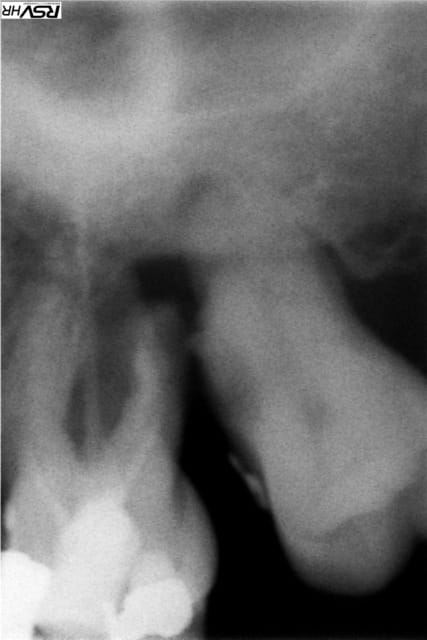

Il s'agit de la 26(radio un peu flou désolé), les racines m et P sont entierement visible en bouche...

Radio u98gdb - Eugenol

Image001 e0kg9q - Eugenol